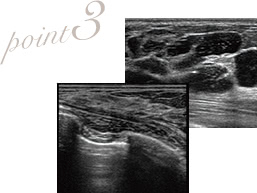

胸に傷を残さないようバッグは脇から抜去する

他院では、取り出しやすいという理由から乳輪やアンダーバストにメスを入れて抜去するところが多いですが、これではバストに傷跡が残ってしまいます。脇だと傷口がシワに沿って、目立つことなく仕上げられる利点があるので、当院ではその方法を採用。技術が必要な箇所ですが、症例数を多く持つTHE CLINICでは可能な施術です。